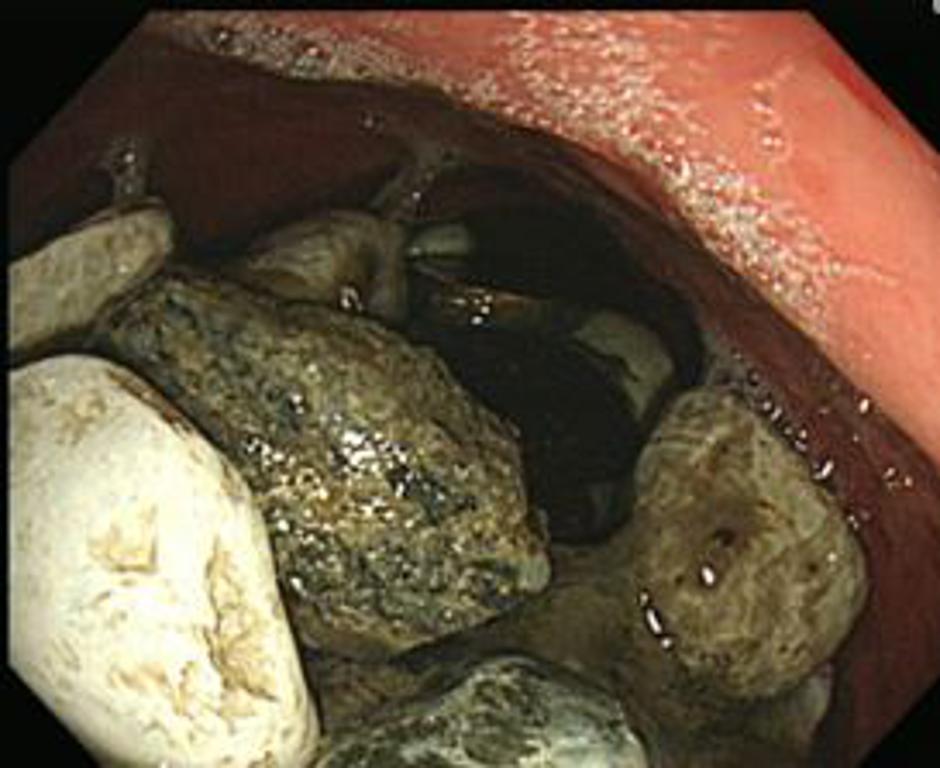

Naslednji dan je ekipa kirurgov počasi in previdno odstranjevala kamenčke, kovance in plastične pokrovčke, je v znanstveni publikaciji American Journal of Medical Case Reports ta nenavadni primer opisal vodilni kirurg  Pyong Wha Choi.

Gastroskopija | Avtor: American Journal of Medical Case Reports American Journal of Medical Case Reports

"Kirurški poseg je bila neizogiben, saj je bilo za endoskopijo preveč tujih teles,"  je zapisal zdravnik.

Dejstvo je, da je zbirka kamenčkov in pokrovčkov, ki so jo potegnili z želodca tehtala kar dva kilograma.